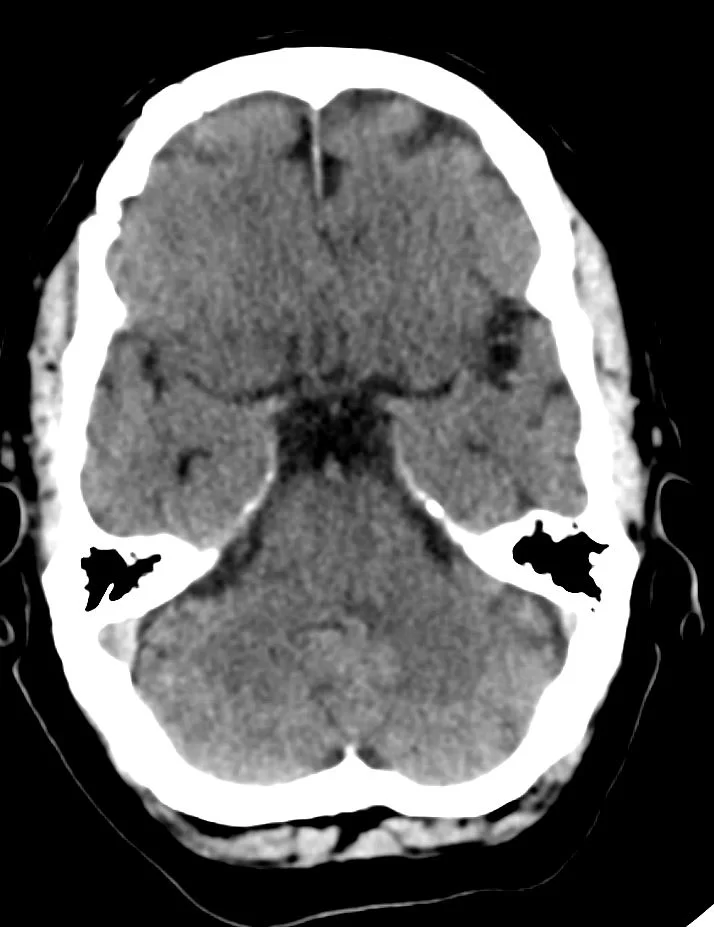

Διενεργήθη δεξιά υπερκόγχιος κρανιοτομία (τομή στο φρύδι) και ολική εξαίρεση της βλάβης.

Η ιστολογική εξέταση ανέδειξε μηνιγγίωμα WHO I.

Μετεγχειρητική Μαγνητική Τομογραφία Εγκεφάλου